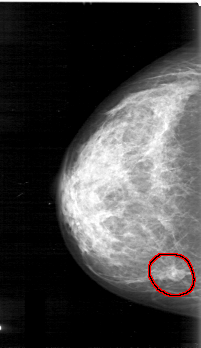

D_4031_1.LEFT_CC

LEFT_CC LINES 4936 PIXELS_PER_LINE 2731 BITS_PER_PIXEL 12 RESOLUTION 43.5 OVERLAY

FILE: D_4031_1.LEFT_CC.OVERLAY

TOTAL_ABNORMALITIES 1

ABNORMALITY 1

LESION_TYPE MASS SHAPE OVAL MARGINS OBSCURED

ASSESSMENT 0

SUBTLETY 5

PATHOLOGY BENIGN

TOTAL_OUTLINES 1

BOUNDARY